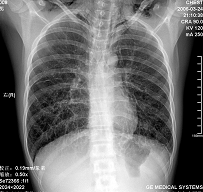

王某某,男,16岁,既往无经常咳嗽、咳痰、胸闷、发热史,活动与同龄儿童相似,三月前突感胸、颈前痛、无喘憋,查体胸骨上皮下气肿,双肺呼吸音对称。胸部dr及ct示纵隔气肿,双肺囊肿。近两月反复出现胸痛、喘憋,无发热、黄痰及痰血,呼吸音减低,胸部dr示双侧自发性(张力性)气胸,胸腔闭式引流治愈。频繁发作,左侧引流两次,右侧引流三次。

1.诊断考虑先天性肺囊肿(囊性肺),自发性、张力性气胸,鉴别支气管扩张,先天性囊性腺瘤样畸形等

从上述x线片、ct片看,先考虑先天性肺囊肿(囊性肺),伴气胸、纵隔积气、皮下积气;先天性囊性腺瘤样畸形,一般中叶很少累及.

先考虑先天性肺囊肿(囊性肺),伴气胸、纵隔积气、皮下积气,胸水.先天性囊性腺瘤样畸形